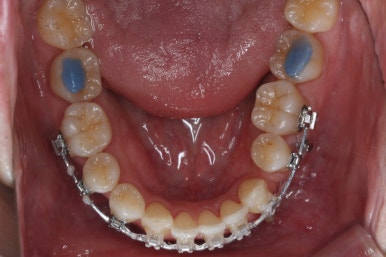

아래 앞니 갯수가 이미 1개 모자라고 좌우 비대칭도 있고 아래앞니도 뒤로 당겨넣어야 하기 때문에 이를 1개 뽑았어요.

이를 뽑은 위치로 앞니도 뒤로 밀어넣어주고 좌우 균형도 맞춰주기로 했습니다.

이 뽑은 자리로 앞니를 쭈욱 밀어넣으며 비대칭도 맞춰주기 위해서 미니스크류(마이크로 임플란트)라고 불리는 작은 나사를 잇몸뼈에 식립했어요.

이를 지지대로 삼아서 치아를 움직이게 됩니다.

아랫니를 계속 당겨주면서 가지런하게 하고 있어요.

어느 정도 진행이 되었다 싶으면 윗니도 장치를 부착해서 가지런하게 해줘요.

아랫니 이 뽑은 자리는 거의 다 다물렸어요.

거꾸로 물리는 앞니도 어느 정도 많이 개선이 되었고요.